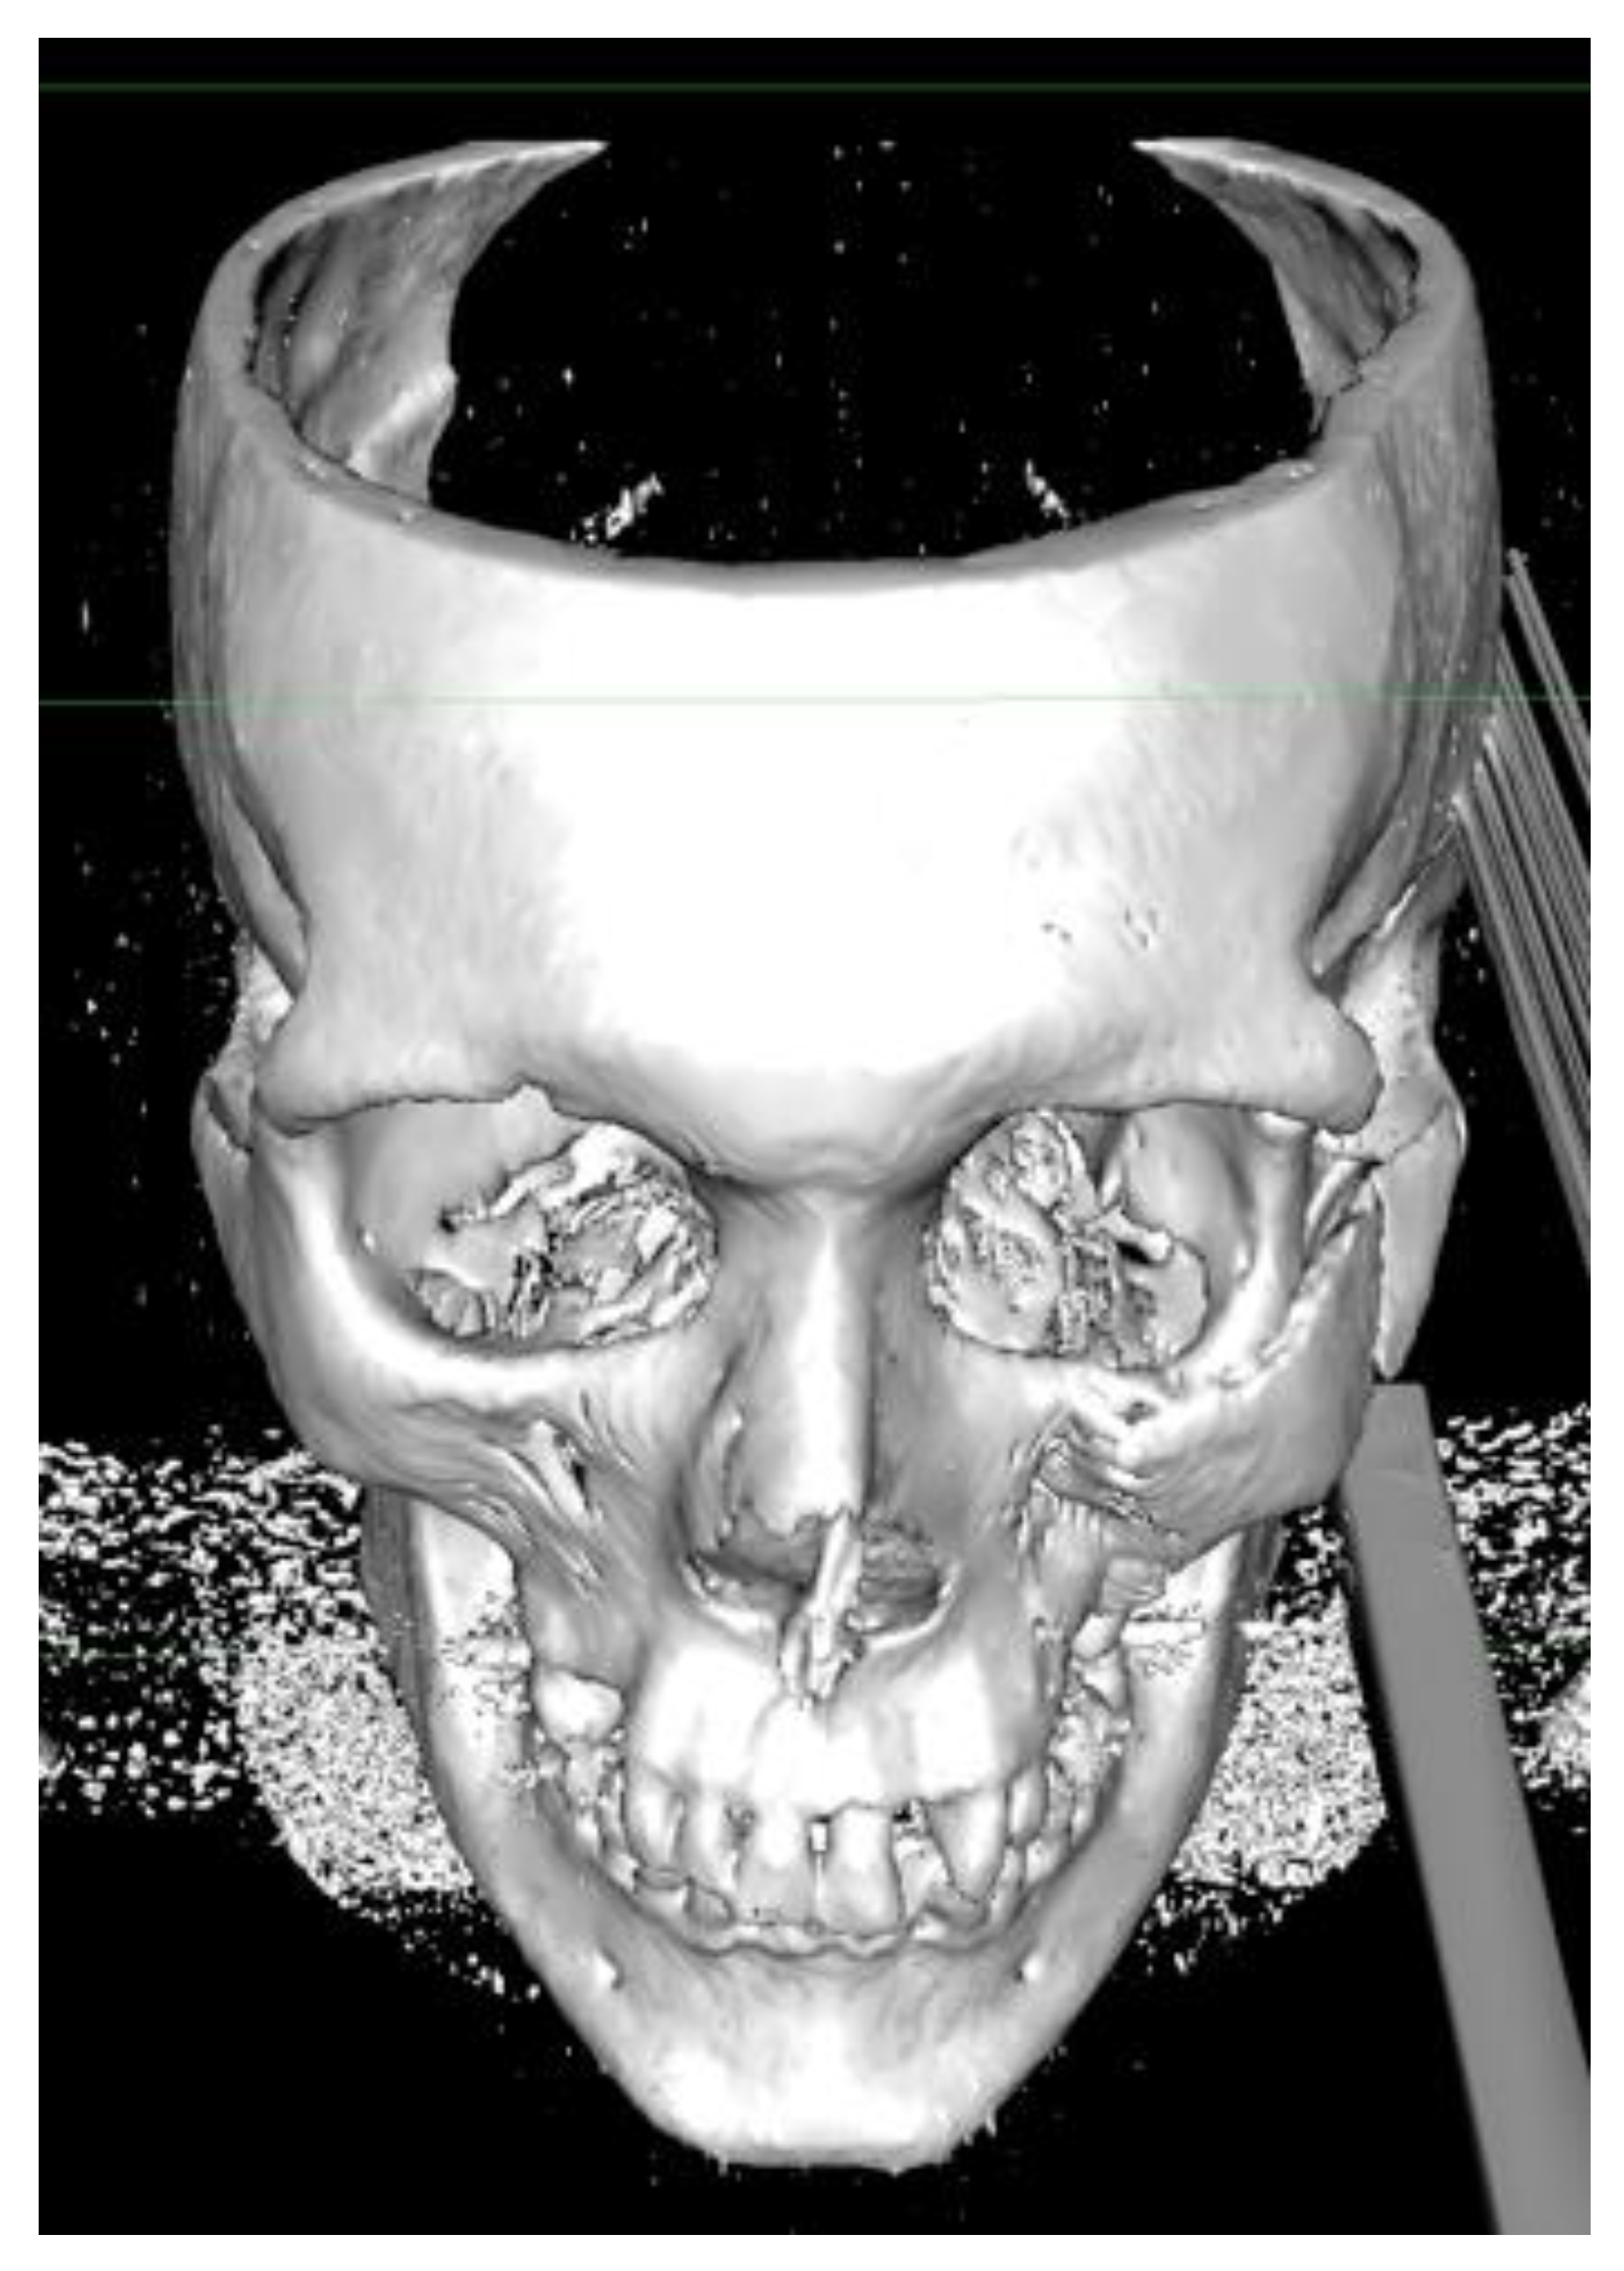

A 36 year-old male suffered from a blunt craniofacial trauma on the left temporal region caused by a baseball bat beating. The patient was admitted to the emergency department and then to the Ward of Maxillo-Facial Surgery. Because of the excessive fractures of the temporal bone along with the skull base and middle cranial fossa, the patient required intense monitoring (Figure 1, Figure 2, Figure 3, Figure 4, Figure 5 and Figure 6). Neurological status was fine; no CSF leak was present. No neurosurgical intervention to lift the displaced bone was used because of the close proximity of the meningeal artery in the fractured temporal bone region, which might cause serious, life-threatening bleeding. Secondly, the displacement was slightly less than 5 mm in total and symptomless. Detailed trauma-CT scans and 3D visualization revealed a fracture of the cranial base, along with the middle cranial fossa vault, cranial displacement of some part of the left frontal bone, and a fracture of the left zygomatic-orbital complex (Figure 7, Figure 8, Figure 9 and Figure 10).

Figure 13. Postoperative 3D-CT reconstruction after stable bone osteosynthesis. After fracture reduction and stable osteosynthesis, no zygomatic bone-coronoid process of the mandible conflict was present.

Figure 14. Postoperative frontal view 3D-CT evaluation indicated good position of the orbital walls and acceptable final results from stable bone osteosynthesis. Red arrow points on proper bone alignement.